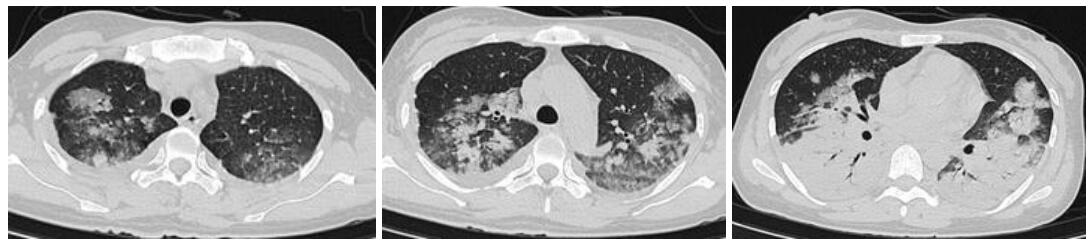

入院查体:体温39 ℃,脉搏87次/min,呼吸30次/min,血压111/75 mmHg(1 mmHg=0.133 kPa);神清,无皮疹,浅表淋巴结无肿大,双肺闻及少许干湿啰音,心律齐,未闻及杂音,腹软,肝脾肋下未触及;胸部CT示两肺感染,见图 1;甲、乙型流感病毒抗原检测阴性。入院诊断:重症社区获得性肺炎。予无创机械通气,莫西沙星抗感染,帕拉米韦抗病毒治疗,效果欠佳,遂转入ICU。入ICU血气:FiO2 70%,pH 7.44,PCO2 30.5 mmHg,PO2 88.2 mmHg,Lac 0.9 mmol/L,PO2/FiO2 126.0,考虑合并急性呼吸窘迫综合征,予气管插管机械通气,右美托美定+丙泊酚镇静、哌拉西林他唑巴坦、奥司他韦、甲泼尼松龙等治疗。复查胸部CT示:两下肺实变。行俯卧位通气,行肺泡灌洗液mNGS检测:鹦鹉热衣原体(序列数773),未检测到病毒及其他细菌,改用多西环素+莫西沙星抗感染。治疗效果好,1周后复查肺CT示病灶吸收明显,见图 2;第10天脱机拔管,转出ICU。

| 两肺片状模糊影,双肺下叶实变渗出病灶较前明显吸收 图 2 病例1入院1周胸部CT结果 |